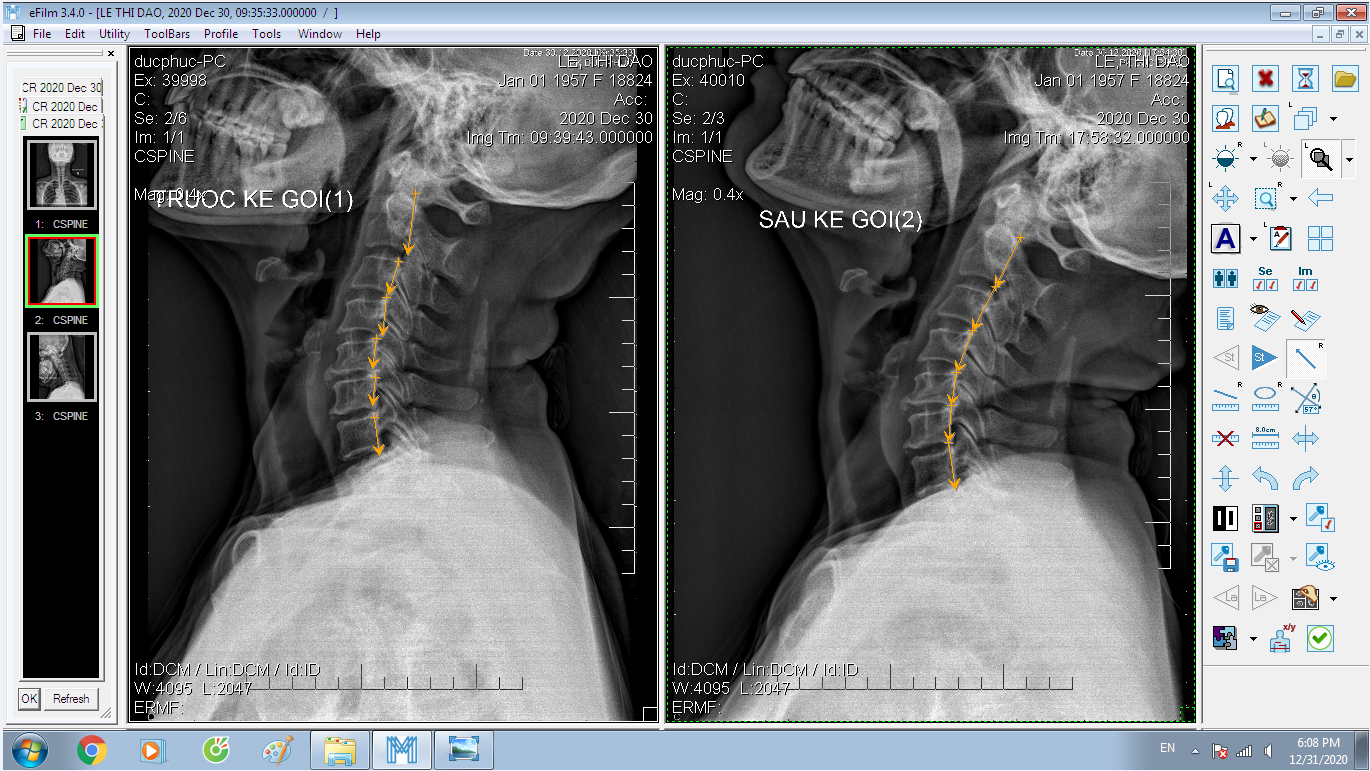

DOCTORLOAN đã thành công trong điều chỉnh xương khớp về đúng vị trí trong thời gian ngắn